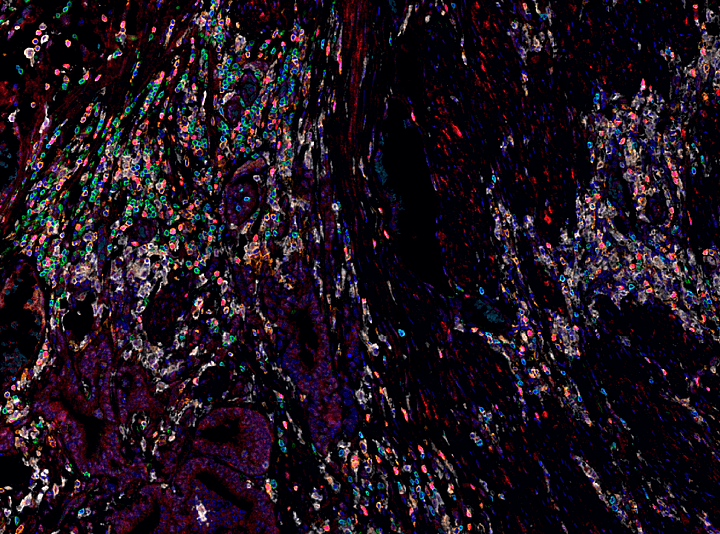

超强大空间分析功能,深入分析挖掘多重荧光免疫组化图像中多维度空间信息

多线程并行批量空间分析轻松实现1000+蛋白空间组学数据分析

荧光定量

空间关系分析